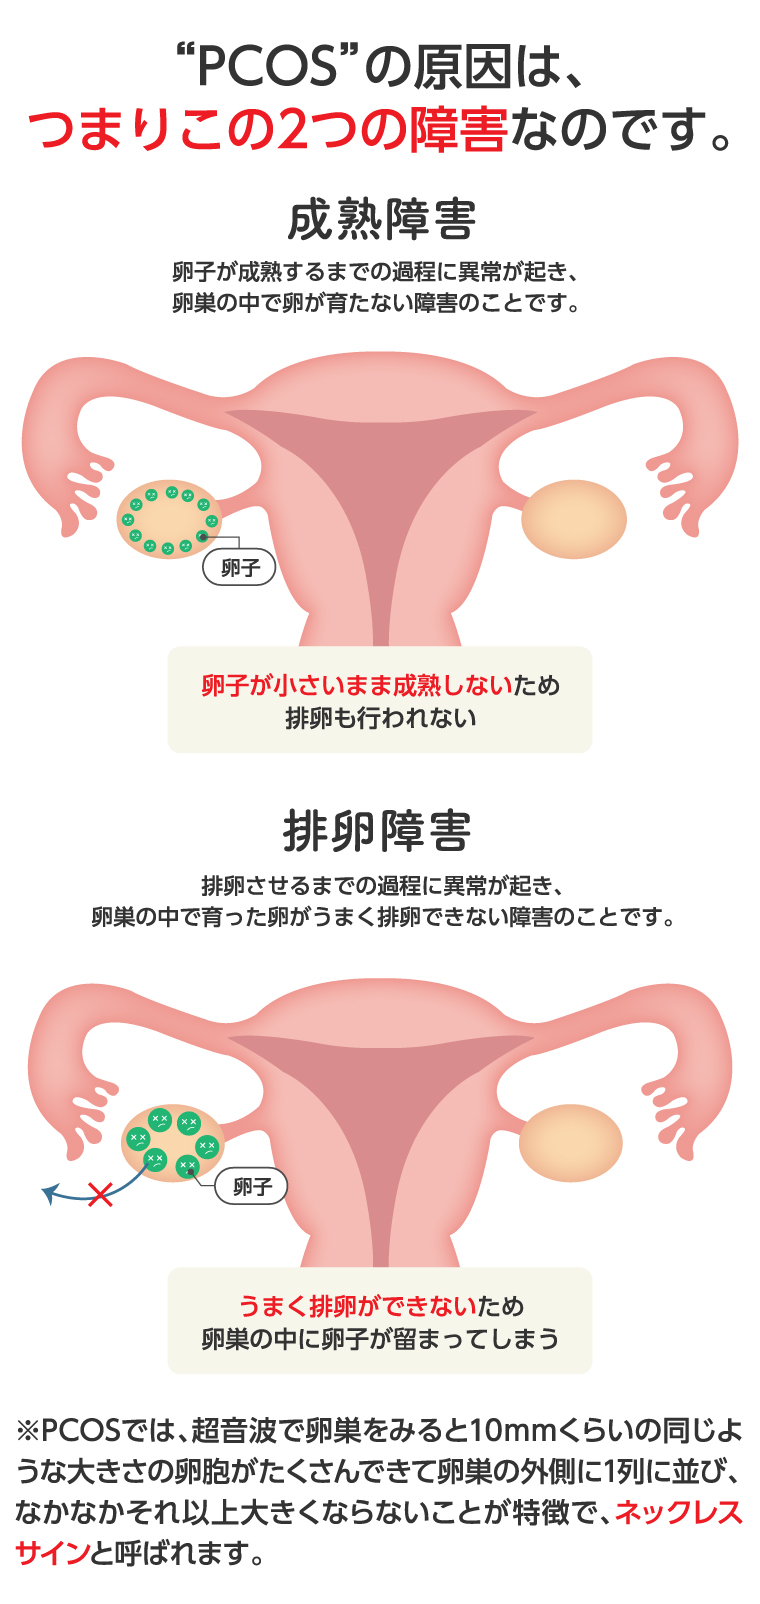

多嚢胞性卵巣症候群〜普段の生活で気をつけること 産婦人科専門医による妊活ガイド

多嚢胞性卵巣症候群(PCOS)でお悩みの方へ 大津市 医療法人 木下レディースクリニック